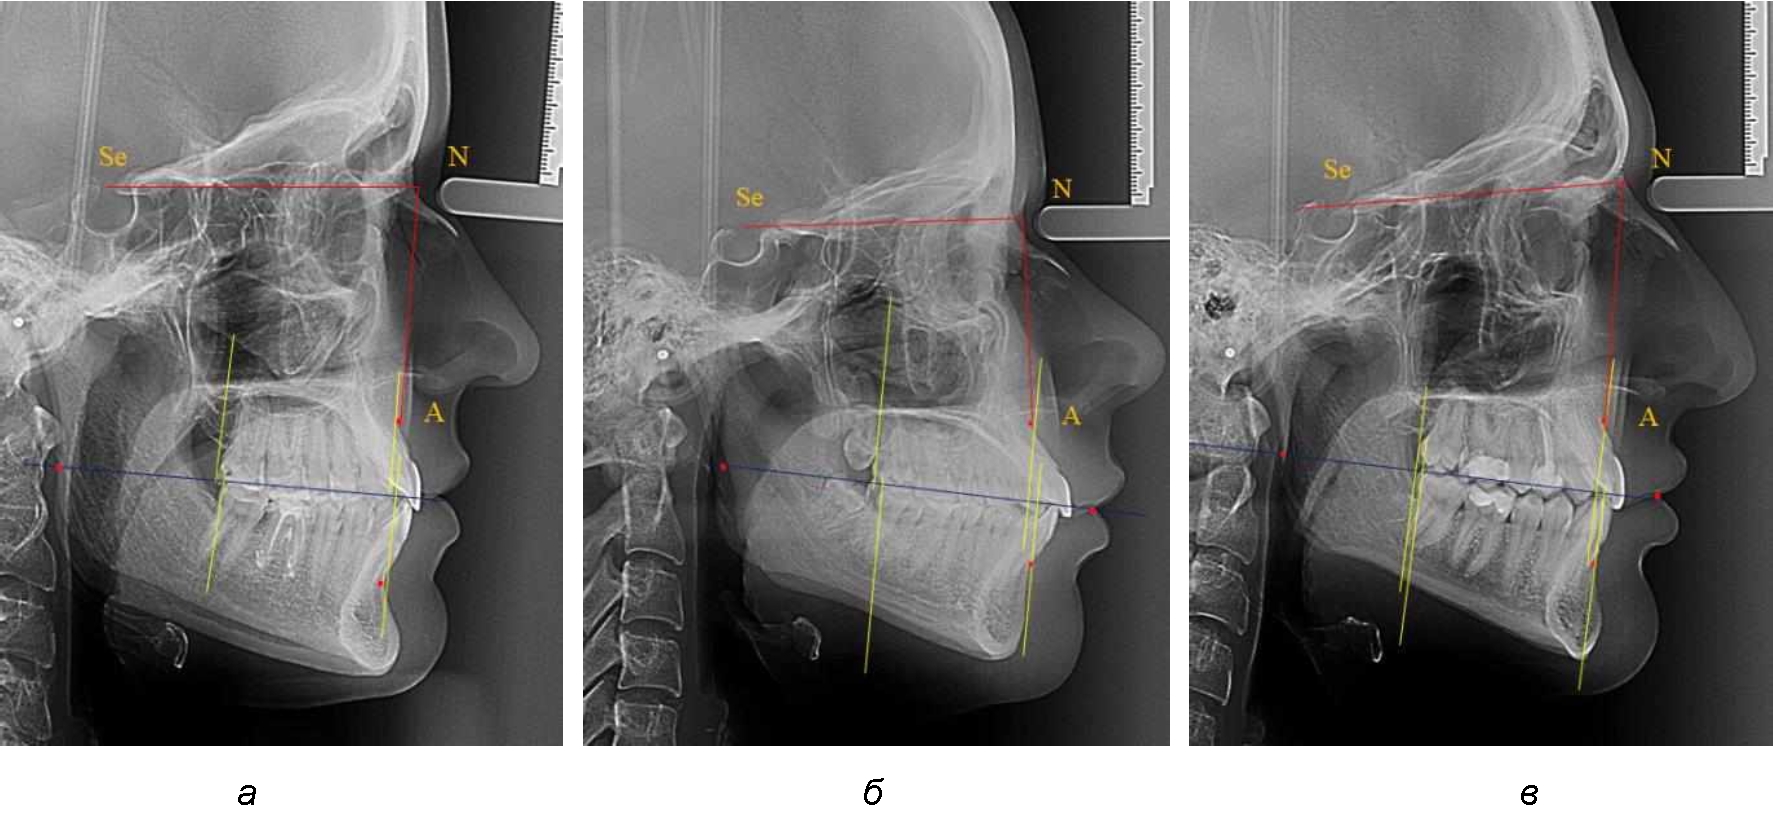

На рентгенограммах устанавливали точки Downs. На верхней челюсти субспинальная точка A(SS) располагалась в наиболее вогнутой точке альвеолярного отростка по переднему его краю. На нижней челюсти супраментальная точка B(SM) соответствовала месту наибольшей вогнутости переднего края альвеолярной части. Окклюзионную линию проводили через контактную точку резцов (vРOcP) и дистальную точку окклюзии второго нижнего моляра (hРOcP). Место пересечения окклюзионной линии с дистальным краем ветви нижней челюсти (ramus mandibule) обозначали как «rmРOcP». Перпендикулярно к окклюзионной плоскости проводили линии из точек «А(SS)» и «В(SМ)», что определяло их проекцию на окклюзионную линию. Аналогично отмечали положения дистальных окклюзионных точек верхней и нижней челюсти (рис. 1).

Рис. 1. Положение основных точек (а) и линейных ориентиров (б) для анализа положения и размеров челюстей

Альвеолярно-дентальный размер верхней челюсти и нижней челюсти оценивали по окклюзионной линии между вертикалями, ограничивающими исследуемые челюсти. Положение верхней челюсти оценивали по величине размера «rmOcP-А», а нижней челюсти по расстоянию «rmOcP-В». Линия смыкания губ обозначалась как точка «sto», вблизи которой проходила окклюзионная линия. Данный ориентир позволял провести окклюзионную плоскость при аномалиях положения резцов в вертикальном направлении, когда была сложность определения резцовой окклюзионной точки (vРOcP).

Рис. 2. Положение апикальных точек и челюстей при нормопозиции (а), антепозиции (б) и ретропозиции (в) верхней челюсти